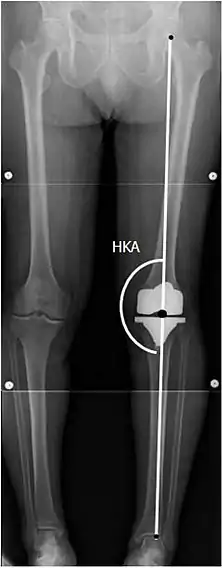

Angles commonly measured before knee replacement surgery: |

To indicate knee replacement in case of osteoarthritis, its radiographic classification and severity of symptoms both should be substantial. Such radiography should consist of weightbearing X-rays of both knees: AP, lateral, and 30 degrees of flexion. AP and lateral views may not show joint space narrowing, but the 30-degree flexion view is most sensitive for narrowing. Full-length projections also are used in order to adjust the prosthesis to provide a neutral angle for the distal lower extremity. Two angles used for this purpose are:

- Hip-knee-shaft angle (HKS),[10] an angle formed between a line through the longitudinal axis of the femoral shaft and its mechanical axis, which is a line from the center of the femoral head to the intercondylar notch of the distal femur.[12]

- Hip-knee-ankle angle (HKA),[11] which is an angle between the femoral mechanical axis and the center of the ankle joint.[12] It is normally between 1.0° and 1.5° of varus in adults.[13]